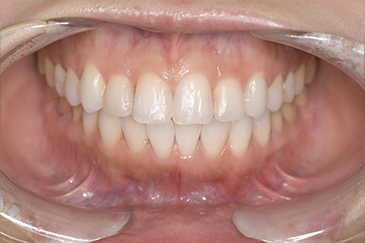

クリーニングの症例

現在の治療費と異なる場合がございます。最新の治療費は料金表をご確認ください。CASE 1

Before

After

基本情報

| 主訴 | 見た目をきれいにしたい |

| 治療期間 | 6ヶ月 |

| 治療費 | ジルコニアボンド(セラミックの被せもの)¥165,000×7(税込み) オフィスホワイトニング4回 ¥4,400×4(税込み) ホームホワイトニング¥11,000 |

| リスク・副作用 | かみ合わせがとても強い方の場合、稀に割れてしまうことがあります。 |

| 先生からの提案 | 上の前歯6本と右下の2番目の歯はセラミックの被せもので治療。 残りの下の前歯5本はプラスチックの材料で虫歯を治療し、 ホワイトニングをおこないました。白くなったご自身の歯の色に合わせてセラミックの 被せものを作成しています。 模型上で完成後をシュミレーションし、上の歯茎の位置をきれいに見えるように 揃えています。(外科処置はしていません) |